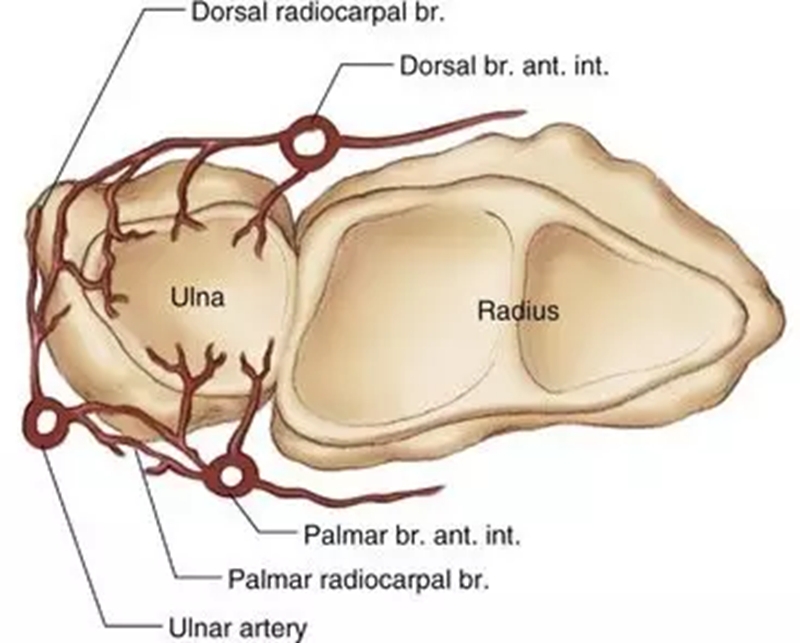

血供

TFCC的周边约20%的区域(桡侧缘除外)有血供,中心约80%的区域无血供。这就决定了TFCC不同部位损伤后具有完全不同的愈合能力,同时也提示不同的分型需采取不同的治疗方式。早期明确损伤的性质以及撕裂的部位对临床治疗方法的选择具有关键性指导意义。